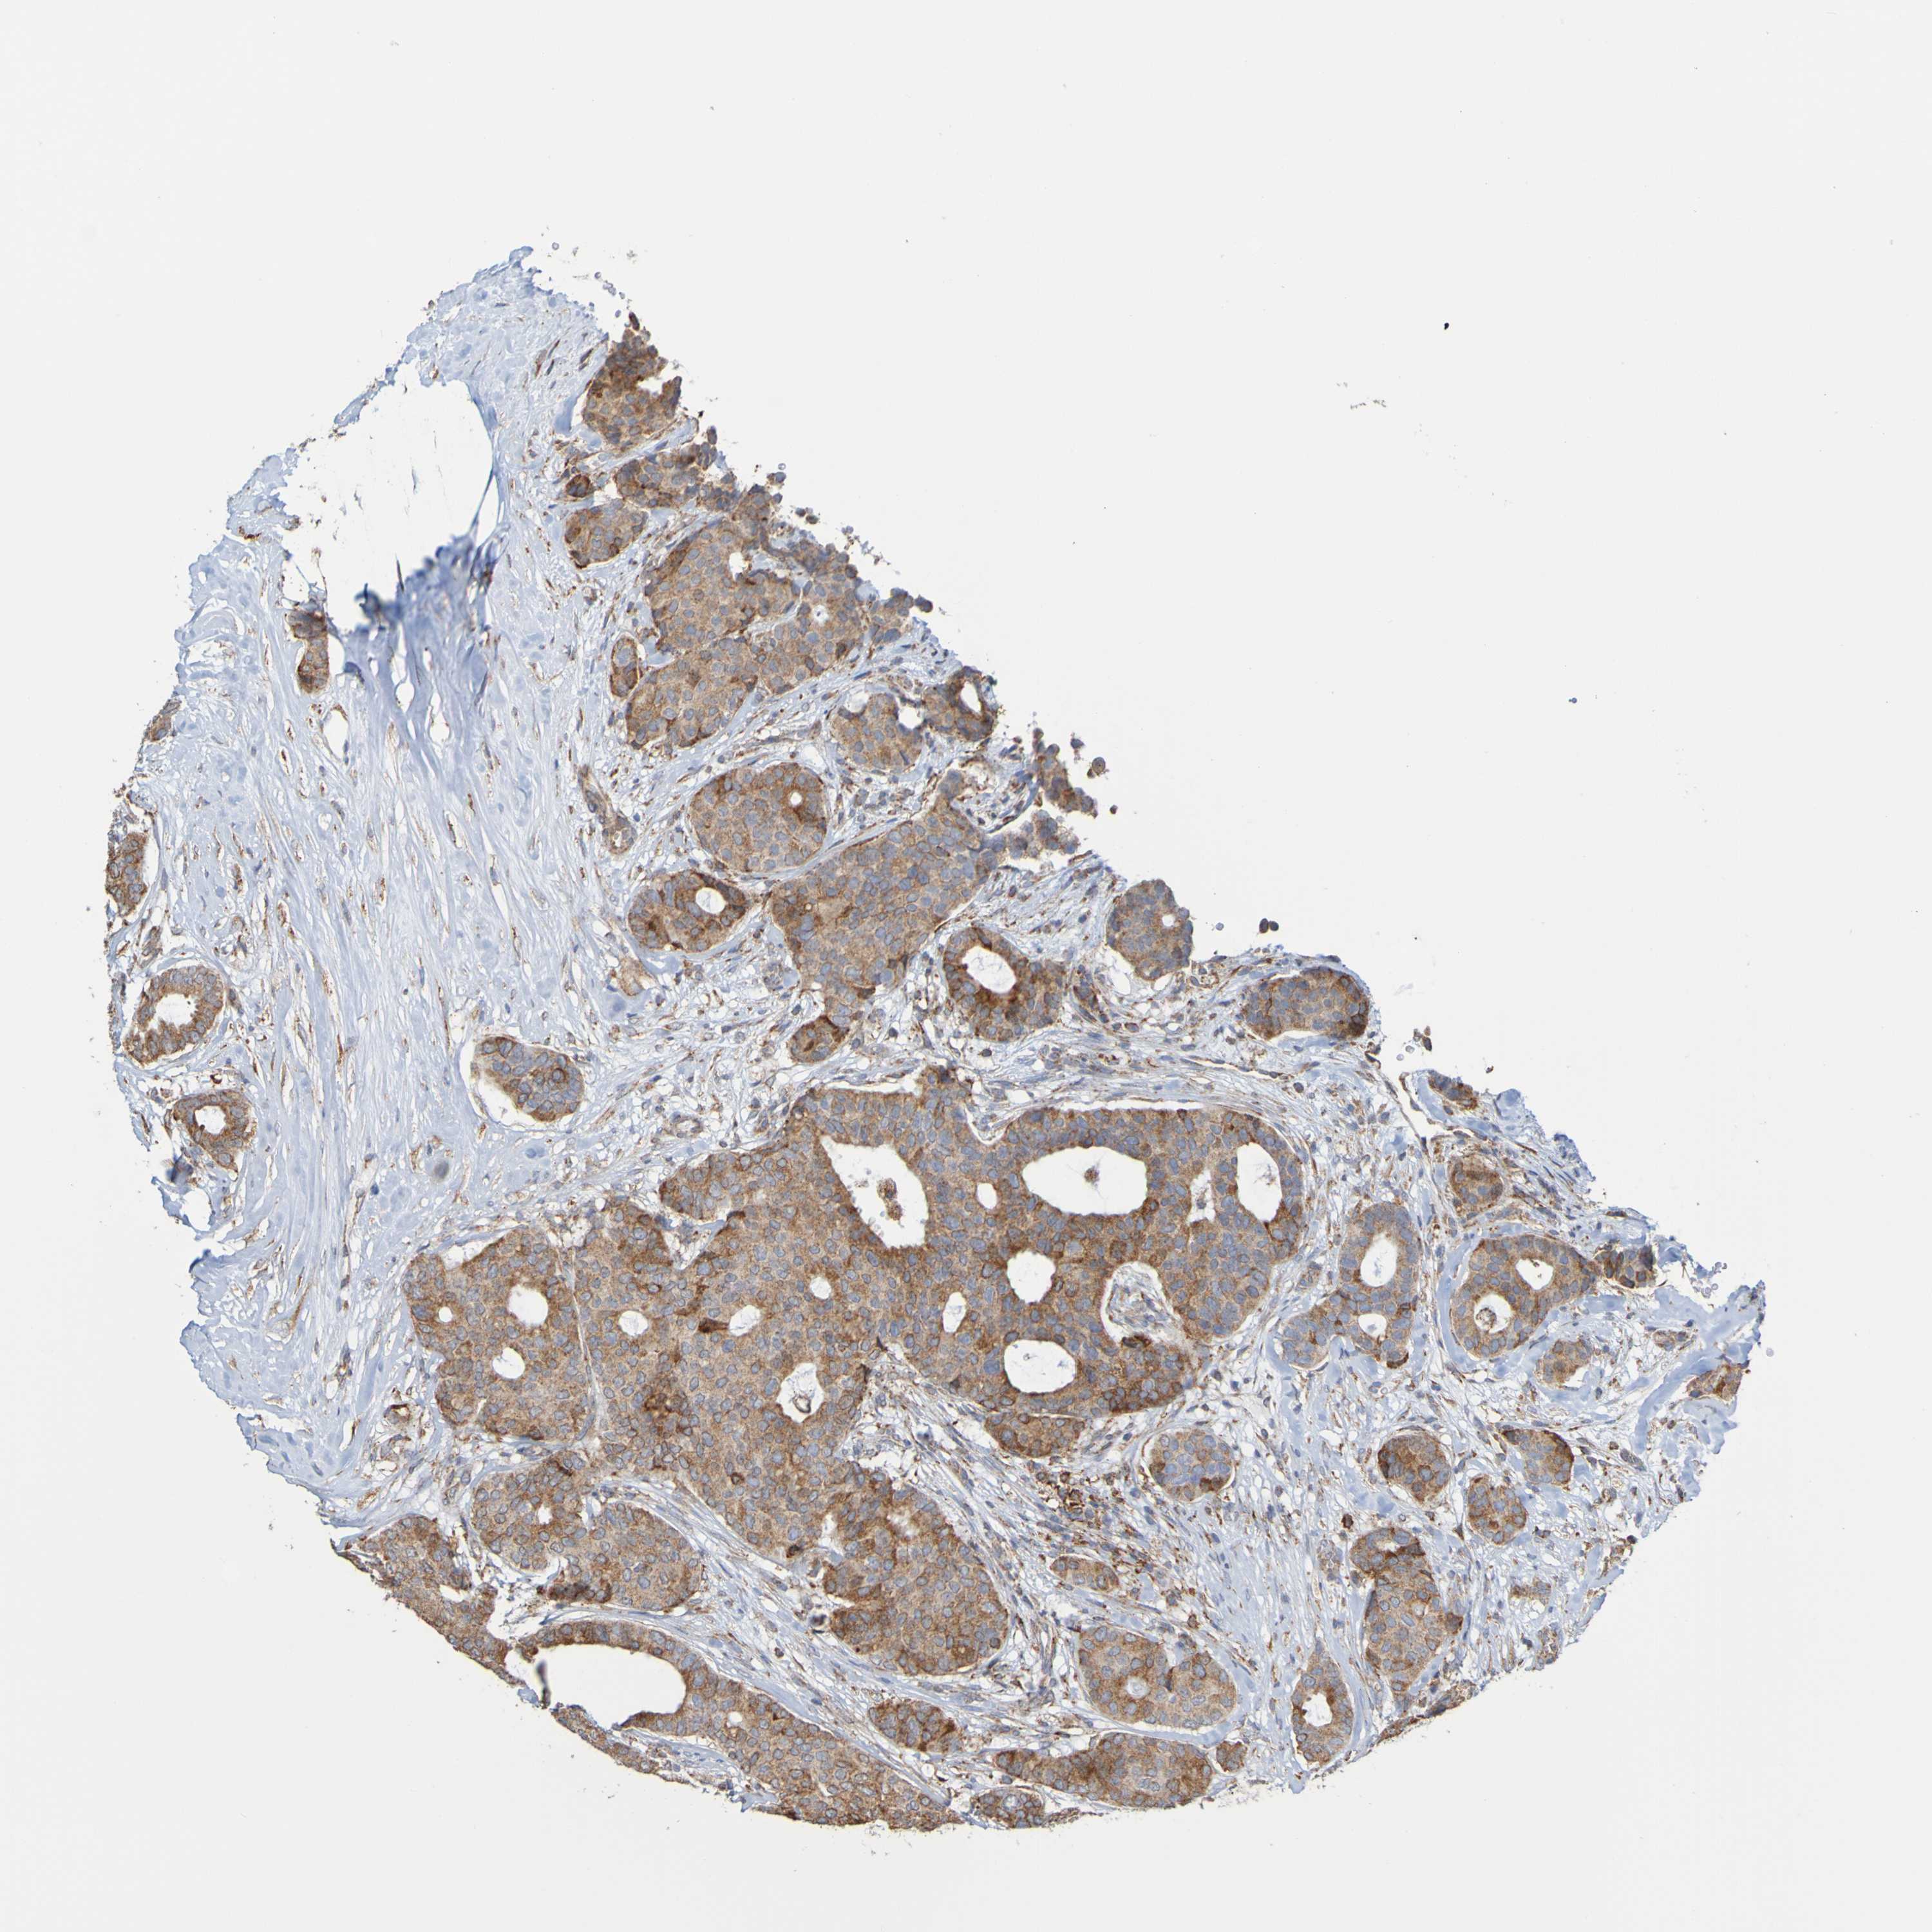

CANCER BREAST CANCER Show tissue menu

BRCA TCGA BRCA VALIDATION PROTEIN EXPRESSION